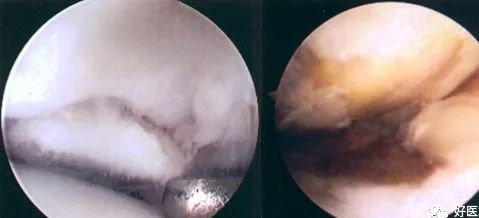

(图中白色部分为髌骨的软骨,发黄的部分是软骨剥脱区域)

关节镜下可将髌骨软化分为5级:

0级:正常关节软骨

Ⅰ级:关节软骨失去珍珠样外观而变得较暗淡,局部软化,肿胀区或纤毛化区的直径<0.5cm。

Ⅱ级:关节软骨软化区内出现毛刷状或纤毛化改变,深达1~2mm,直径≤1.3cm。

Ⅲ级:软骨的毛刷状或纤毛化改变达关节软骨厚度一半以上,直径>1.3cm,关节软骨表面类似蟹肉样改变,表面有多发软骨碎片附着其下的软骨。

Ⅳ级:关节软骨全层受侵,软骨下骨暴露,表现为进展期髌股关节炎。

Ⅰ~Ⅱ级为早期,主要保守治疗。

Ⅲ~Ⅳ级为进展期,需手术及关节镜治疗。